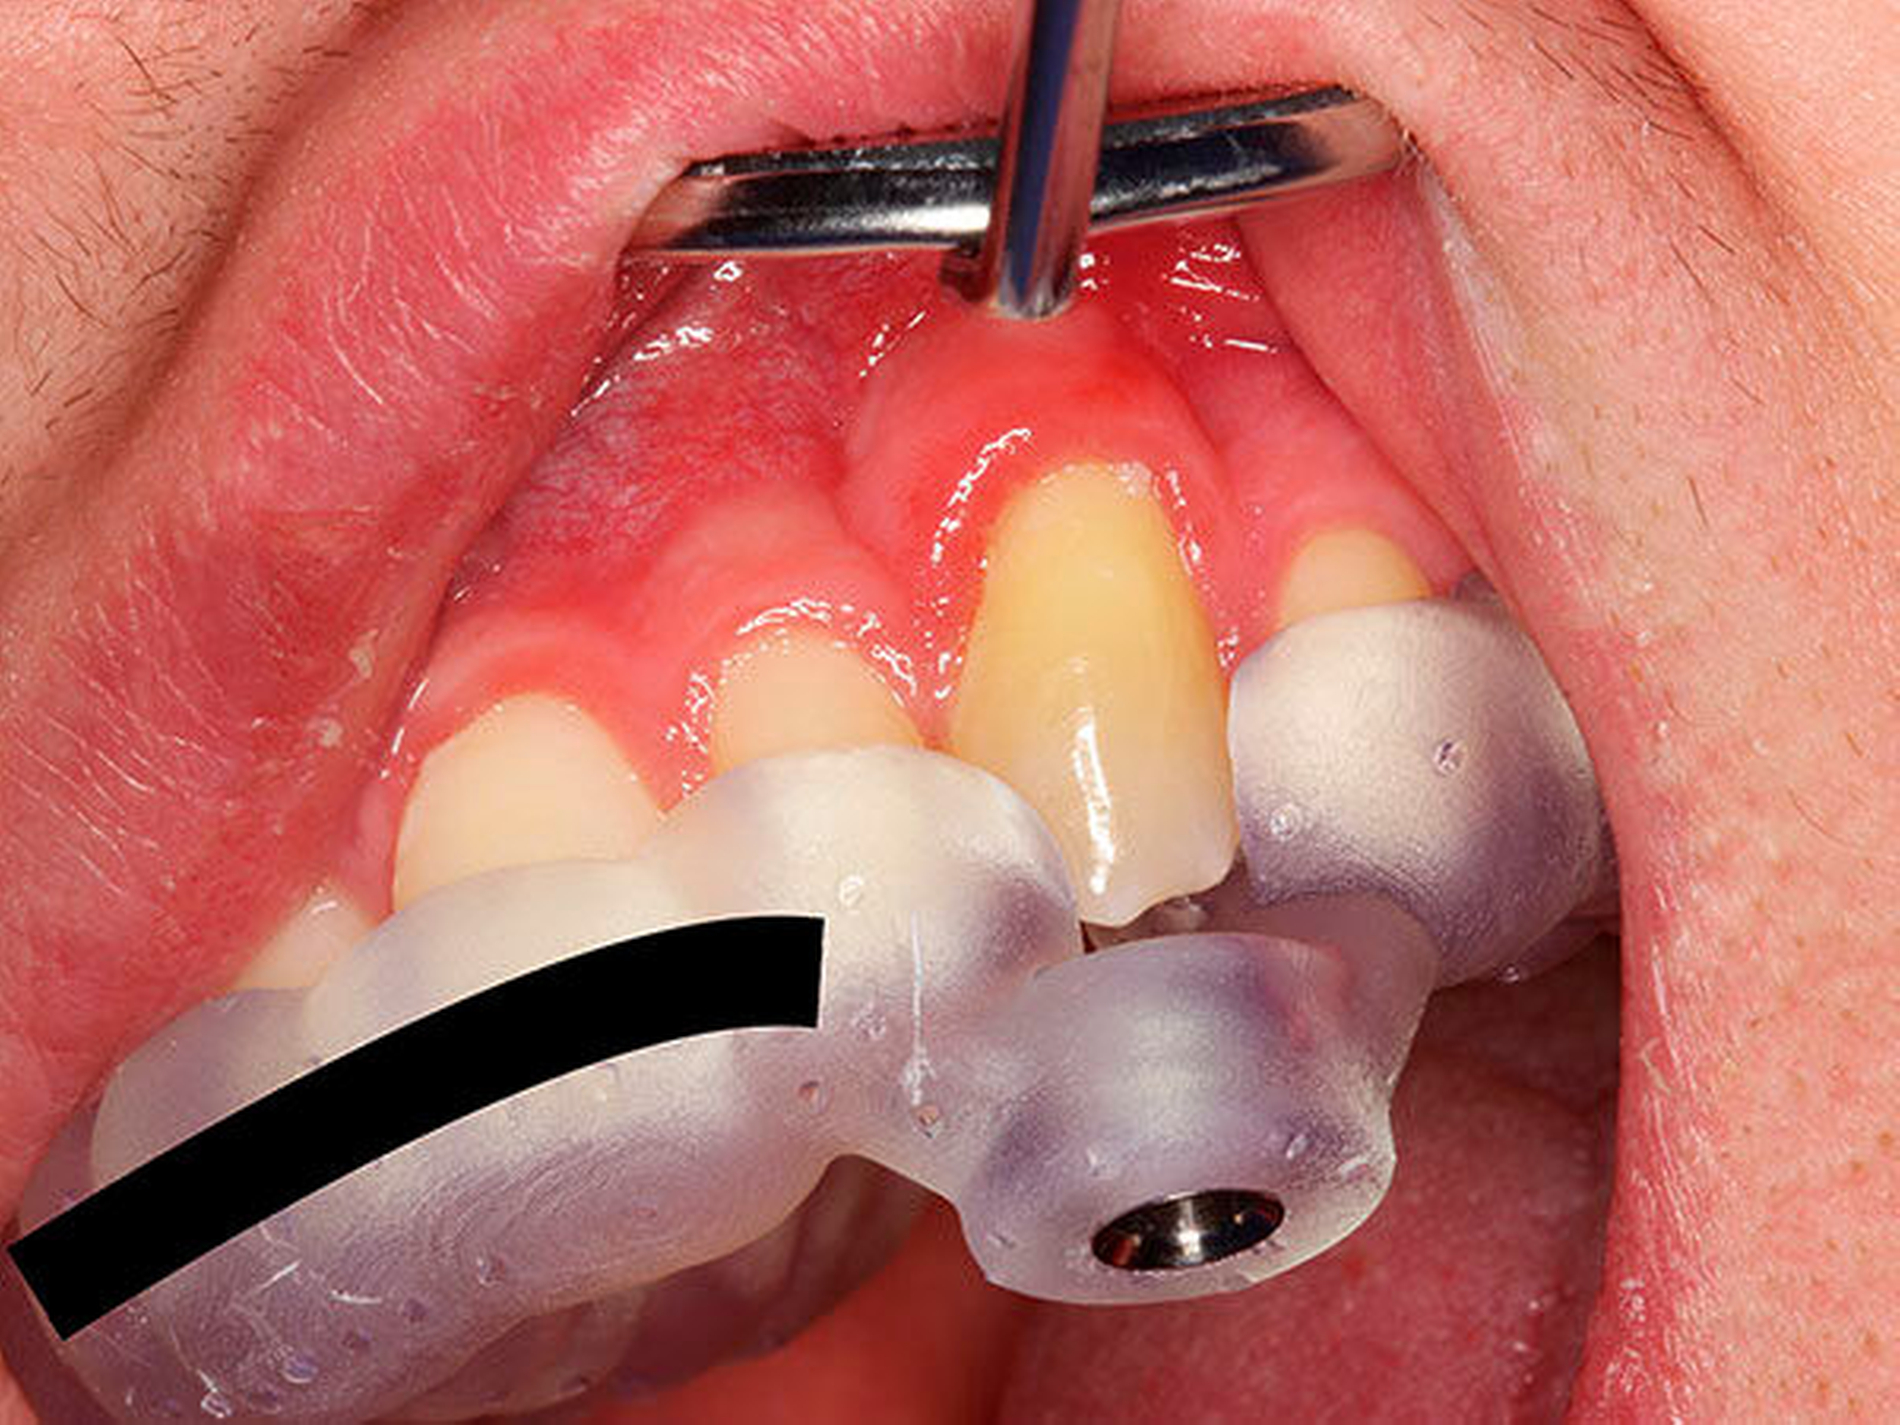

In der folgenden Sitzung wurde die Schiene angepasst (Abbildung 10), die Trepanationsöffnung ergänzt und die Bohrung mittels Endoseal-Bohrer auf die zuvor am DVT geplante Tiefe vorgenommen. Nach erfolgter Bohrung wurde der Kofferdam angebracht und das erschlossene Kanalsystem mit einer ISO 10 C-Feile sondiert (Abbildung 11). Die Endometrie ergab 23,5 mm. Eine Röntgenkontrastaufnahme mit einer ISO 15 K-Feile wurde angefertigt (Abbildung 12). Die mechanische Wurzelkanalpräparation erfolgte mit Reciproc Blue 25 und 40 (VDW, München), die Desinfektion mit NaOCl 5 Prozent und EDTA 17 Prozent. Die Perforation wurde mit Total Fill BC Root Repair Material (FKG, La Chaux-de-Fonds, Schweiz) abgedeckt (Abbildung 13). Im Anschluss wurde eine Masterpointaufnahme angefertigt (Abbildung 14), der Wurzelkanal mit Total Fill BC Points und Sealer (FKG, La Chaux-de-Fonds, Schweiz) biokeramisch abgefüllt (Abbildung 15) und adhäsiv verschlossen. Bei der klinischen Nachuntersuchung nach vier Wochen war der Zahn symptomlos.